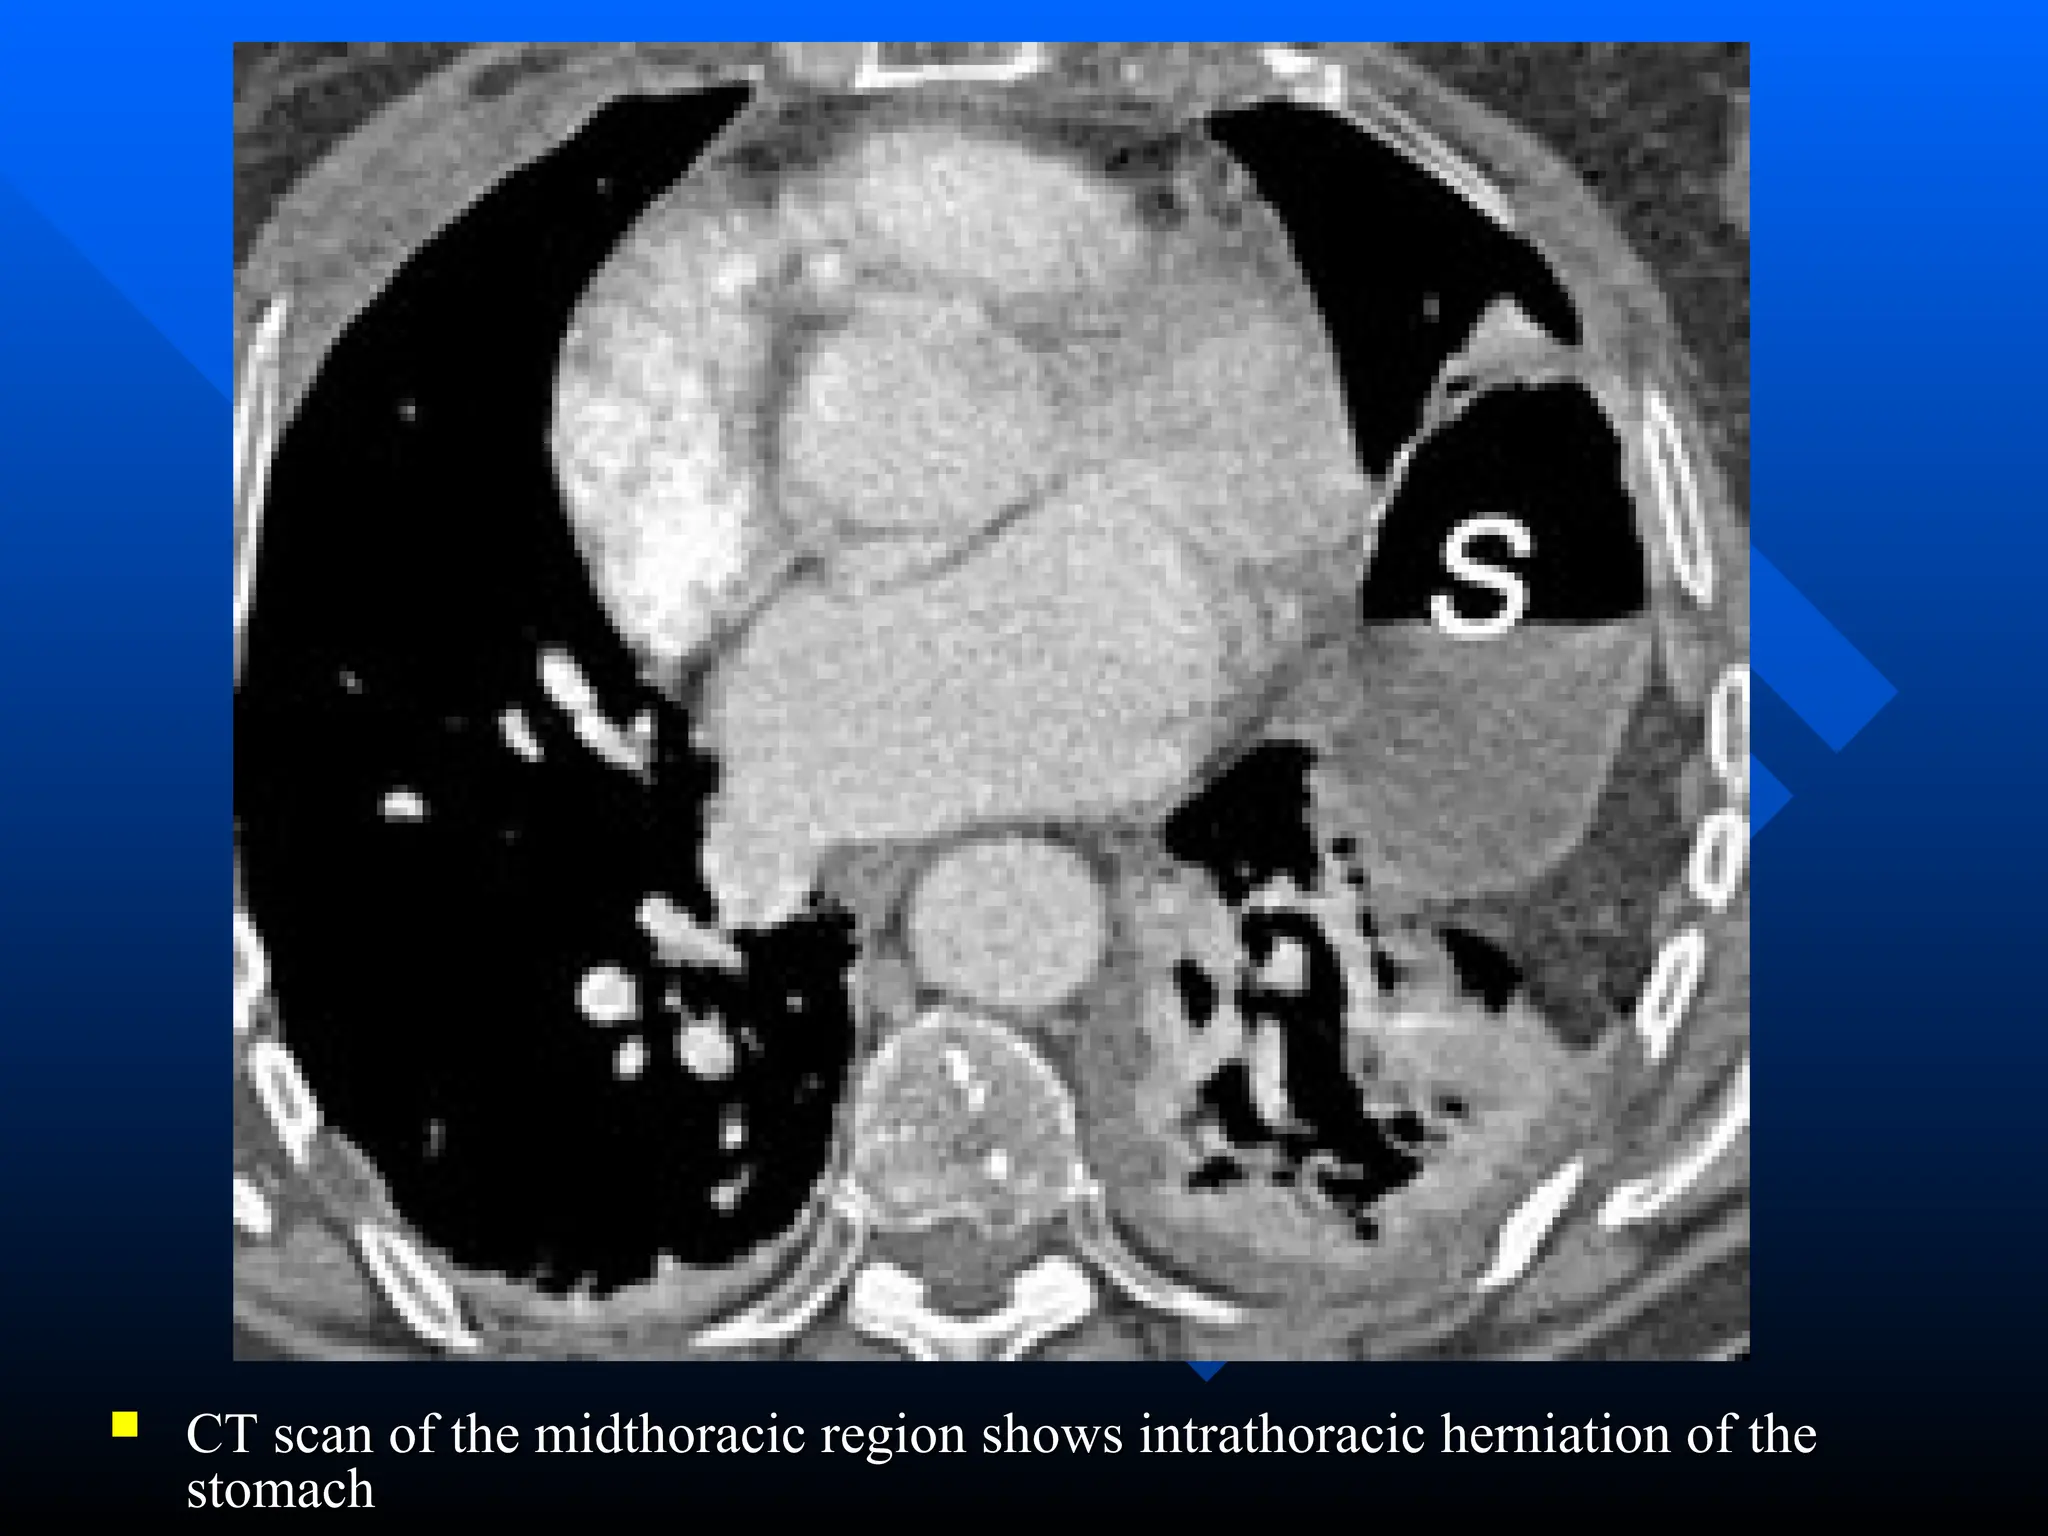

 CT scan of the midthoracic region shows intrathoracic herniation of the

CT scan of the midthoracic region shows intrathoracic herniation of the

stomach